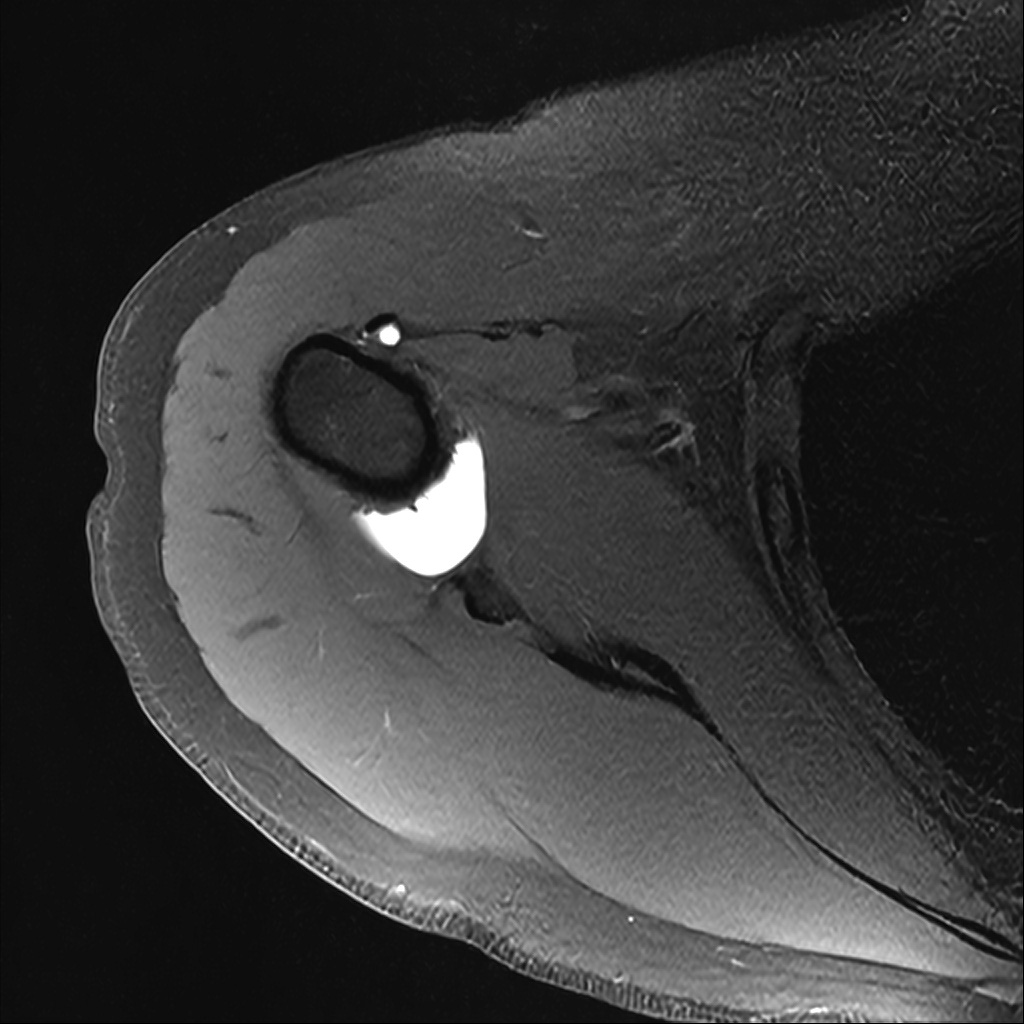

Mri 단면 영상으로 보아 어깨 관절 부위에서 이상 신호가 관찰되고 이는 관절 와순 파열의 가능성을 시사할 수 있습니다.

하지만 이영상만으로 정확한 진단은 불가능하고 정밀한 판단을 위해선 전체 시퀀스와 영상의학과 전문의의 공식판독이 필요합니다 특히 와순 파열은 위치와 동반 병변에 따라 해석이 달라집니다!